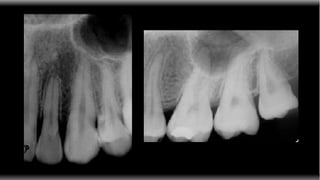

INTERPRETAÇÃO RADIOGRÁFICA UTILIZANDO NEGATOSCÓPIO E JANELA Acerto médio: Janela - 6,6 Negatoscópio - 10 Makdissi, J. J Ir Dent Assoc. 2002;48(4):123-4

INTERPRETAÇÃO RADIOGRÁFICA UTILIZANDONEGATOSCÓPIO E JANELA Acerto médio: Janela - 6,6 Negatoscópio - 10 Makdissi, J. J Ir Dent Assoc. 2002;48(4):123-4